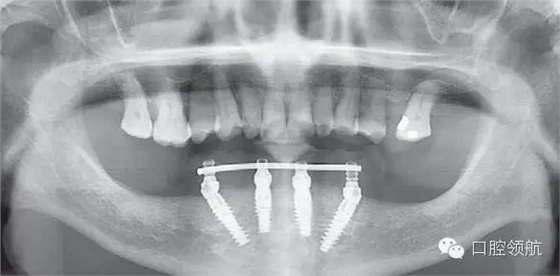

下頜為十?dāng)?shù)年前制作的三組金屬烤瓷橋修復(fù)體。右下4、5、7帶缺失的6;右下3、1及左下1、2帶缺失的右下2;左下3、4、5、8帶缺失的6、7,左下8修復(fù)后牙齒自然脫落,全景片無左下8的影像。幾乎所有的余留牙周圍的骨質(zhì)均吸收到根尖1/3。臨床上三組下頜金屬烤瓷橋均有較大幅度的松動(圖6-7,圖6-8)。

圖6-8 下頜術(shù)前全景片

患者為64歲女性,自述下頜咬合無力,牙齦經(jīng)常出血,有反復(fù)腫脹史,要求拔除后種植修復(fù)。